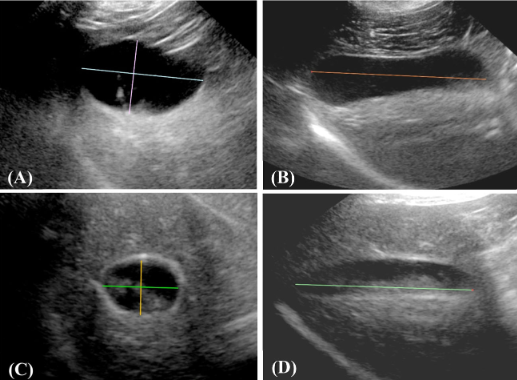

CT 촬영을 통해 3차원적 용적을 계산했으면 좋겠지만 반려견에서 CT 촬영은 마취가 필요하기 때문에 약물에 의한 담낭 영향으로 검사 신뢰도를 훼손할 수 있어 초음파로 진행한 실험이다.

이 검사를 직접할 것은 아니기에 결과만 보자면

고지혈증이 담낭의 확장과 담낭 질환을 유발할 수 있다는 결론이다.